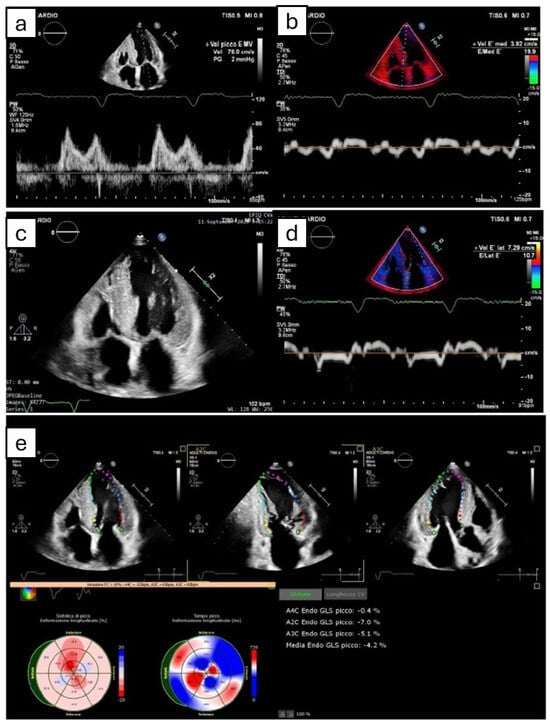

3.1. Left Ventricle

- Phelan, D.; Collier, P.; Thavendiranathan, P.; Popovic, Z.B.; Hanna, M.; Plana, J.C.; Marwick, T.H.; Thomas, J.D. Relative apical sparing of longitudinal strain using two-dimensional speckle-tracking echocardiography is both sensitive and specific for the diagnosis of cardiac amyloidosis. Heart 2012, 98, 1442–1448. [Google Scholar] [CrossRef] [PubMed]

- Wali, E.; Gruca, M.; Singulane, C.; Cotella, J.; Guile, B.; Johnson, R.; Mor-Avi, V.; Addetia, K.; Lang, R.M. How Often Does Apical Sparing of Longitudinal Strain Indicate the Presence of Cardiac Amyloidosis? Am. J. Cardiol. 2023, 202, 12–16. [Google Scholar] [CrossRef] [PubMed]

- Rapezzi, C.; Aimo, A.; Pavasini, R. Longitudinal strain in the management of cardiac AL amyloidosis: Do we need it? Eur. Heart J. 2022, 43, 342–344. [Google Scholar] [CrossRef] [PubMed]

- Cohen, O.C.; Ismael, A.; Pawarova, B.; Manwani, R.; Ravichandran, S.; Law, S.; Foard, D.; Petrie, A.; Ward, S.; Douglas, B.; et al. Longitudinal strain is an independent predictor of survival and response to therapy in patients with systemic AL amyloidosis. Eur. Heart J. 2022, 43, 333–341. [Google Scholar] [CrossRef]

- Huntjens, P.R.; Zhang, K.W.; Soyama, Y.; Karmpalioti, M.; Lenihan, D.J.; Gorcsan, J., 3rd. Prognostic Utility of Echocardiographic Atrial and Ventricular Strain Imaging in Patients with Cardiac Amyloidosis. JACC Cardiovasc. Imaging 2021, 14, 1508–1519. [Google Scholar] [CrossRef]